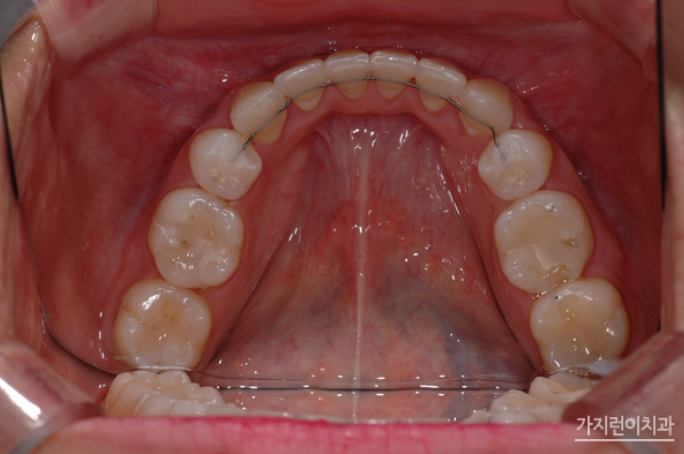

상악은 설측교정방식으로 하악은 순측교정방식으로

해당 환자분의 경우 잘 드러나 보이는 상악은 교정장치를 치아의 뒤에 부착하는 설측교정방식으로, 입술에 가려져 상대적으로 덜 부각되어 보이는 하악은 순측교정 방식으로 진행했습니다. 옥니를 교정하기 위해서는 치아를 이동시켜 다시 바깥 방향으로 각도를 조절해야 하기 때문에 충분한 힘을 받을 수 있도록 미니 스크류를 식립하여 교정용 고무줄을 연결했는데요. 상악 역시 앞으로 돌출되어 나온 부분을 뒤로 밀어 넣어야 하기 때문에 미니스크류를 식립하여 효과적으로 힘이 전달될 수 있도록 하였습니다.